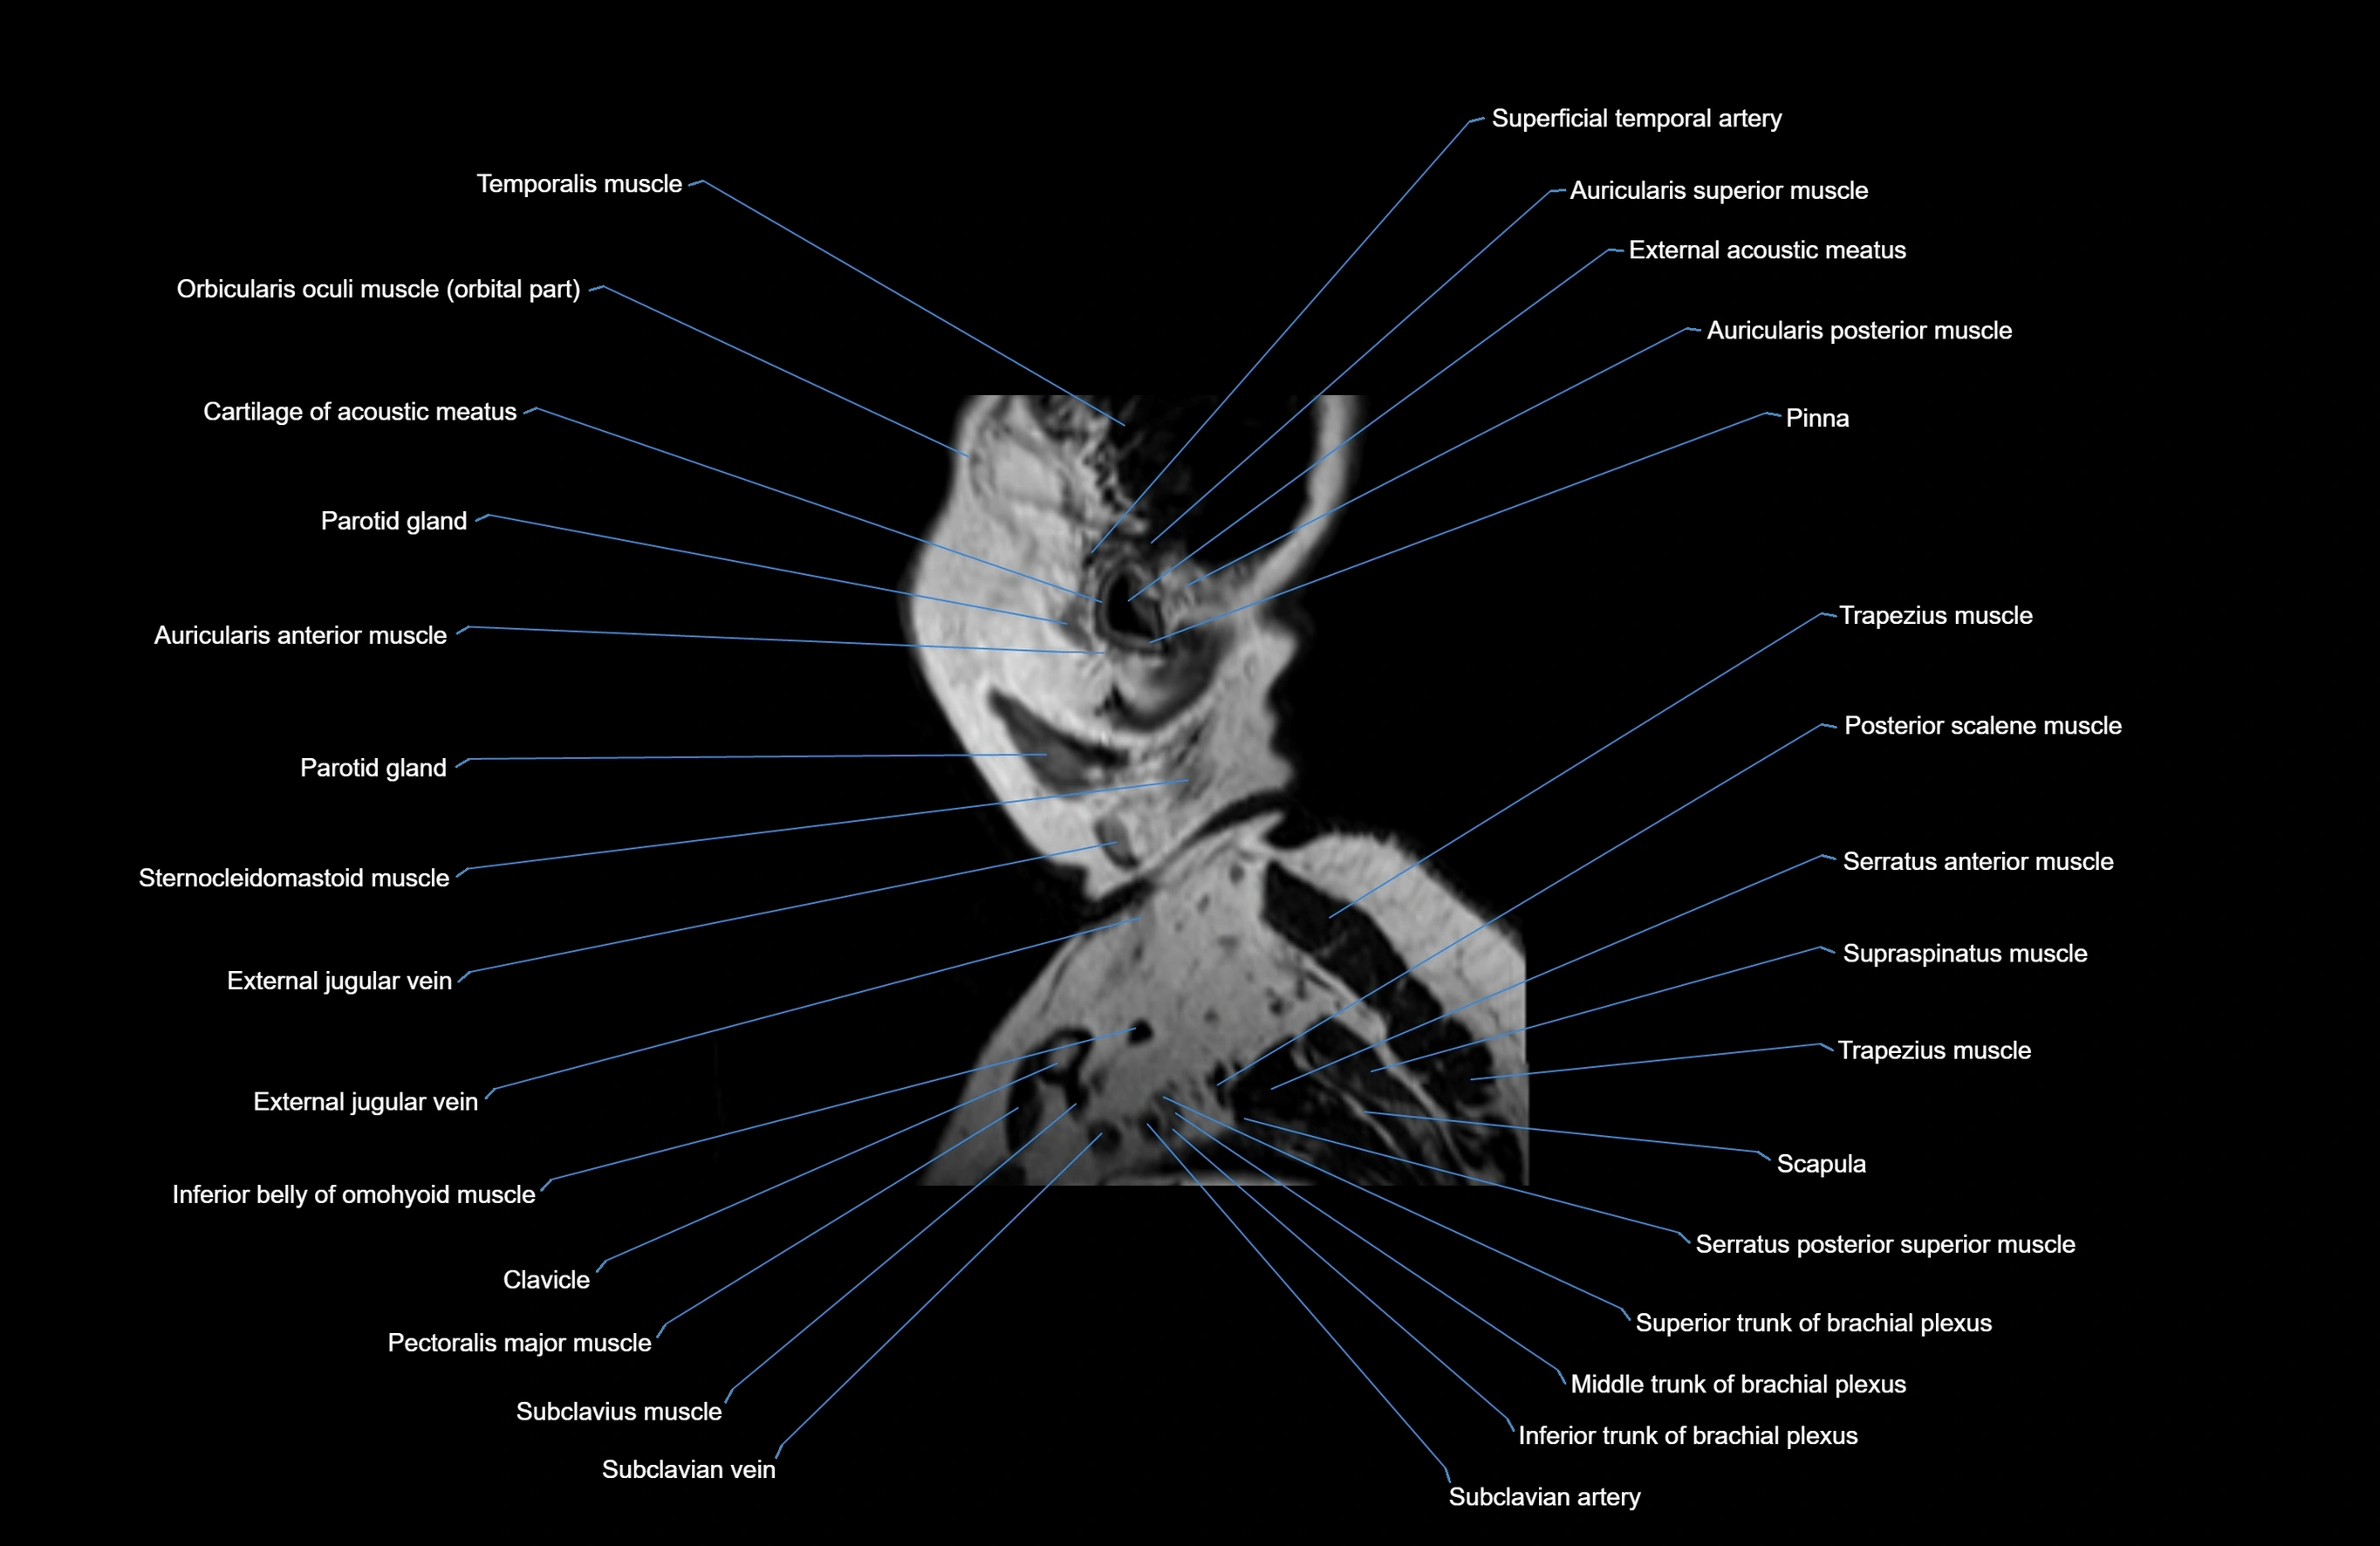

- Auricularis anterior muscle

- Auricularis posterior muscle

- External acoustic meatus

- Inferior belly of omohyoid muscle

- Parotid gland

- Pectoralis major muscle

- Scalenus posterior muscle (Posterior scalene muscle)

- Scapula

- Serratus anterior muscle

- Serratus posterior superior muscle

- Sternocleidomastoid muscle

- Subclavian artery

- Subclavius muscle

- Superficial temporal artery

- Supraspinatus muscle

- Temporalis muscle

- Trapezius muscle